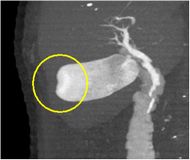

造影CT矢状断像(胆嚢がん)